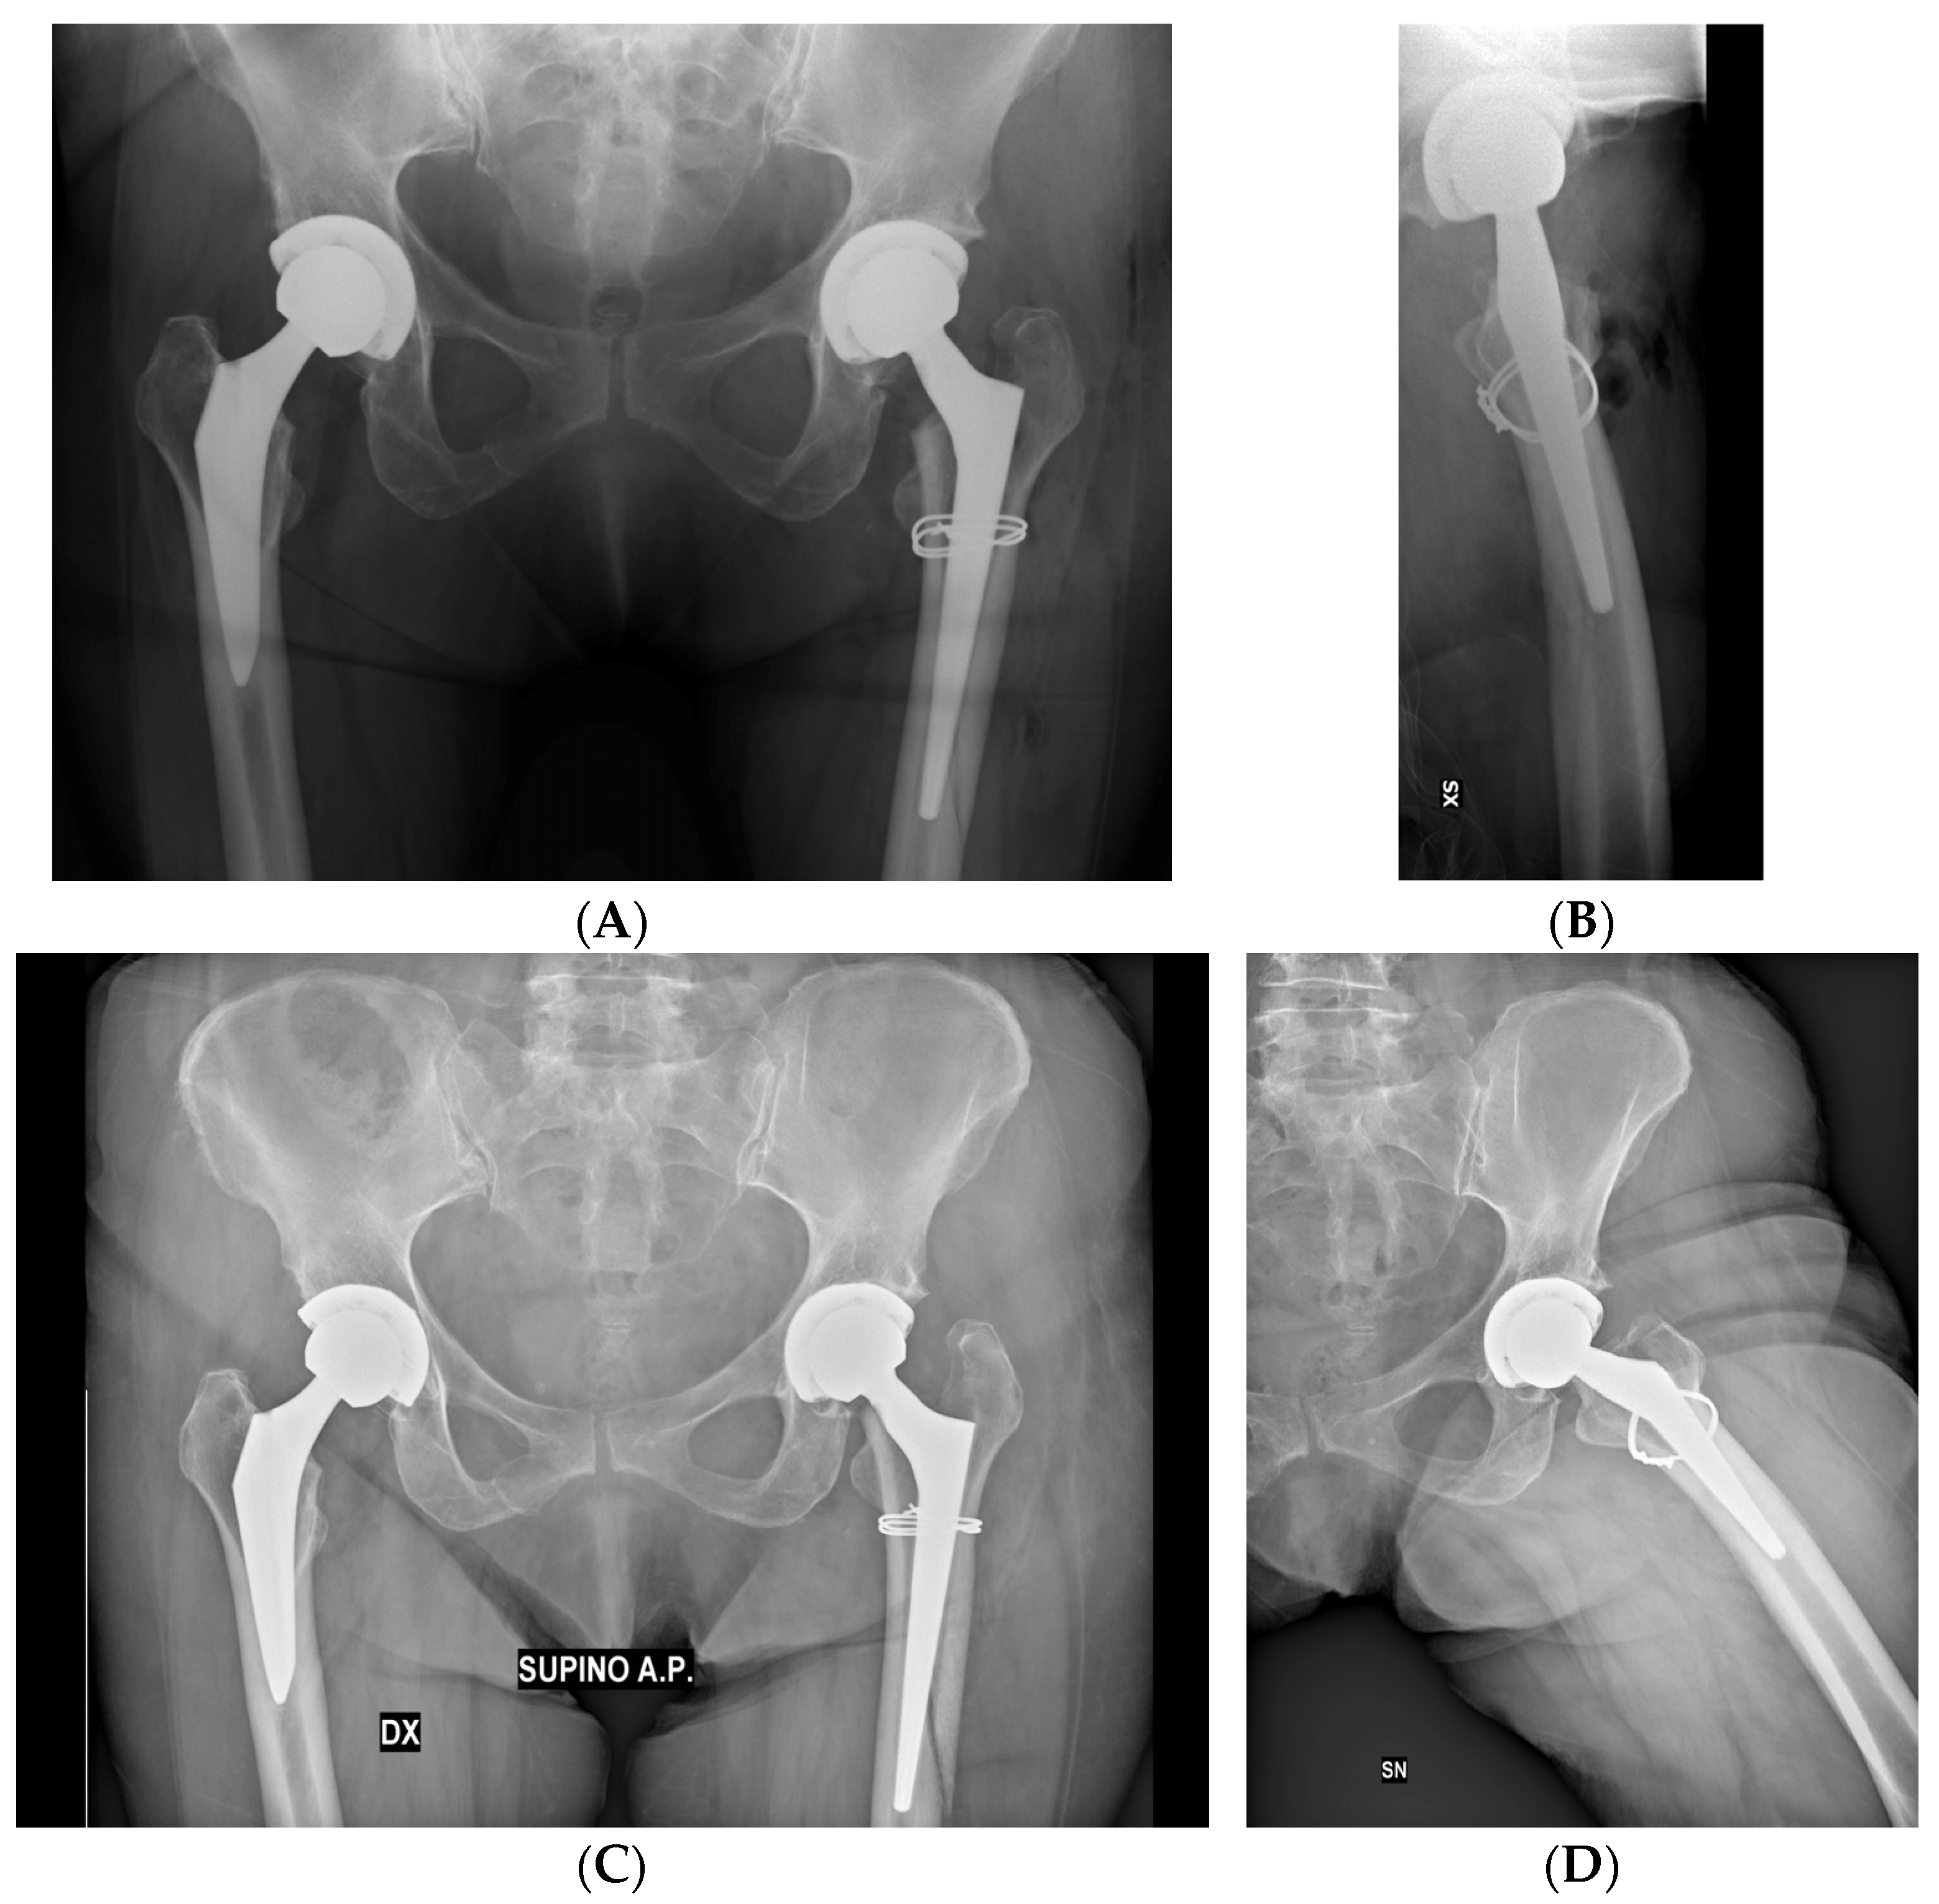

Two implant-related complications were observed in the present cohort (5.41% of the population), both occurring during the first 30 days following the THA: one case of stem loosening and dislocation in a female over 65 years of age (2.70%), and one case of nonunion of the PPHF (2.70%). The first patient underwent revision arthroplasty (RA) within the first 6 months following operation, whereas the second one did not experience significant impairment in hip functionality and did not require revision surgery up to the present time.

The mean HHS and LLD were subject to significant postoperative improvement, as reported in Table 7. Radiographic examples of a successful treatment and a failure model are displayed in Figure 2 and Figure 3.

The stem mobilization rate within one year for our cohort was 2.70% (n = 1). The event was most likely due to a flawed classification of an IOPFF with stem instability as VB1, along with poor adherence of the patient to postoperative recommendations.

Figure 3. (A,B) Postoperative radiographs evidence the intraoperative VB1 fracture of a 71-year-old female, treated with double metal cabling during THA. (C,D) Follow-up radiographic evaluations of the same patient at 6 months exhibit signs of implant loosening and stem mobilization, probably caused by flawed intraoperative lesion classification and poor adherence of the patient to the recommendations given by the surgeon. Reintervention with revision arthroplasty was necessary to address this postoperative complication.